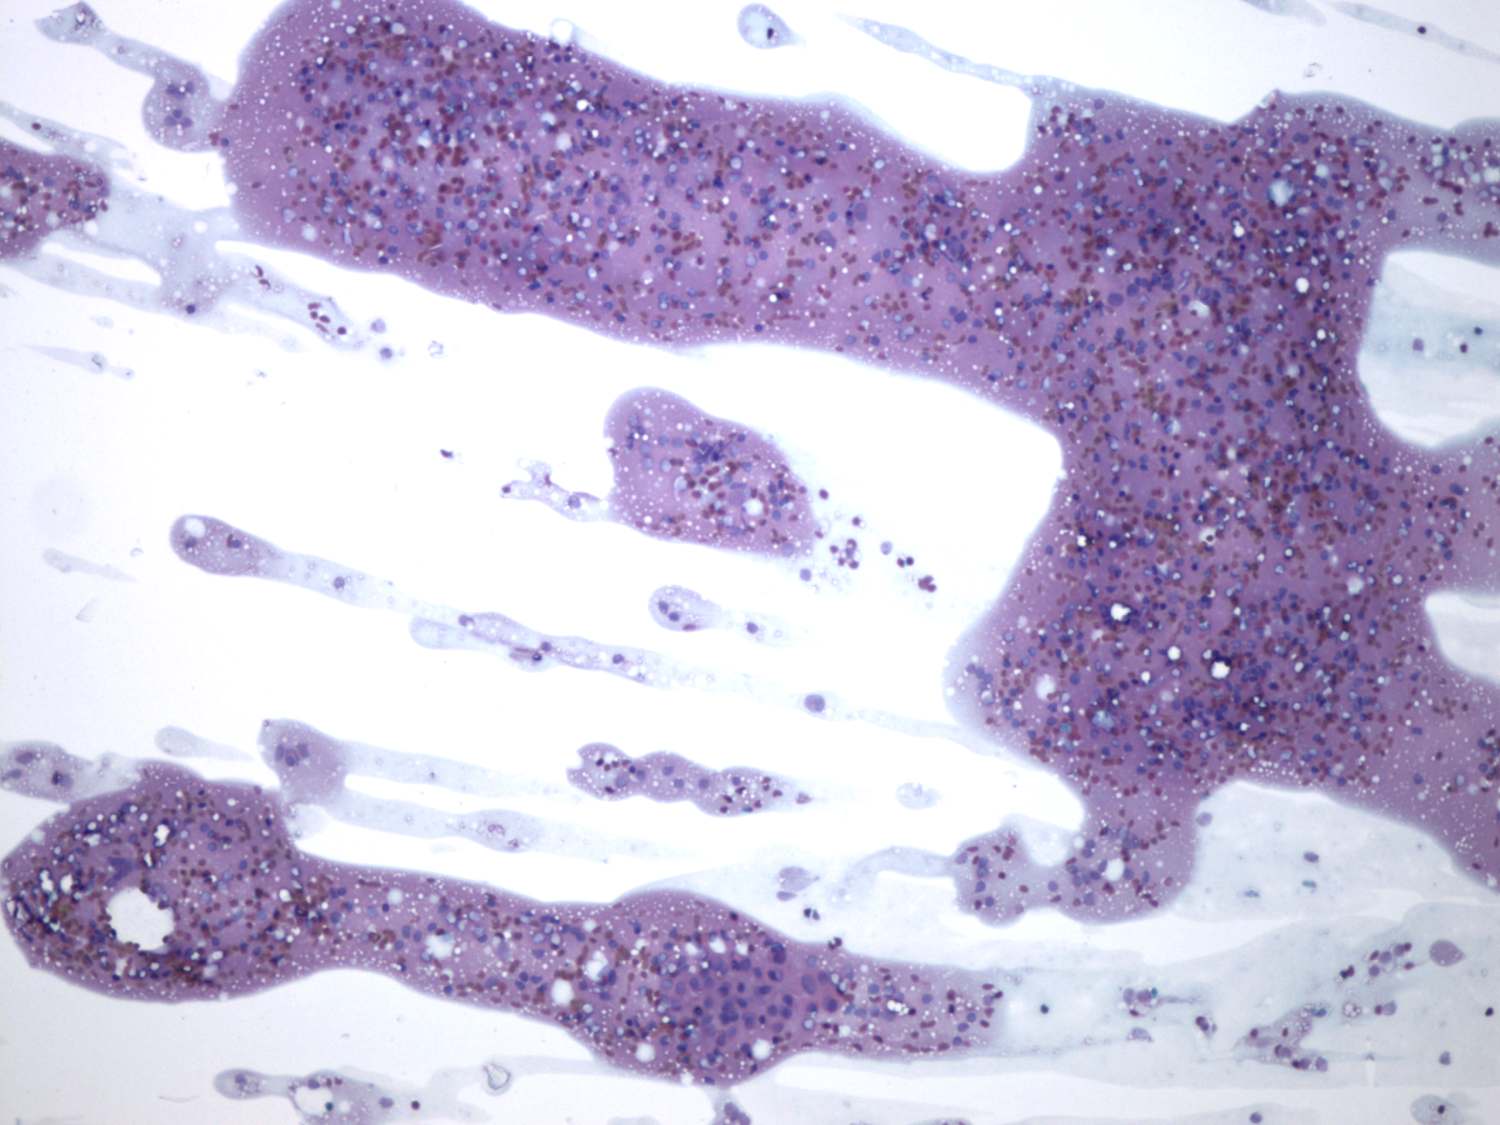

Subacute granulomatous thyroiditis - case 827 (cytologic picture 1)

Pap-smear, 100x.   Lymphoid cells and groups of thyrocytes predominate the smear.